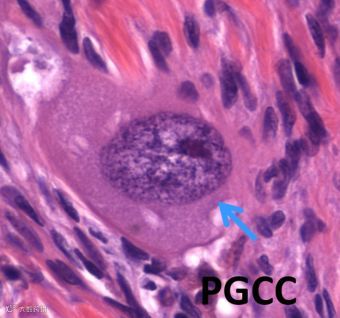

那么成熟的体细胞又是如何去分化而获得恶性生长潜能呢?基于课题组最近八年的工作,我们已经发表了一系列文章证明多倍体肿瘤巨细胞/Polyploid giant cancer cells (PGCCs,图2 ),作为一个特殊的亚群,有卵裂球样癌症干细胞的特性。

我们的实验结果证实了PGCCs可以分化为肿瘤间质的成纤维细胞, 血管内皮细胞及红细胞,中性粒细胞等等[7-10]。所以PGCCs并非传统意义上的肿瘤干细胞,并且是可在显微镜下观察到的。 由此,我们的理论可以很好地解释肿瘤组织器官样生长,也是我们病理学上的肿瘤形态和显微镜下观察所见,如三阴性乳腺癌,高级别的卵巢癌, 高级别肉瘤等肿瘤组织都可以看到PGCCs,并且也可以解释这些不同类型肿瘤发生的过程。

图2. 卵巢组织中正常纤维细胞可以通过内复制产生单核瘤巨细胞继而形成肿瘤。图示单核瘤巨细胞(PGCC)。